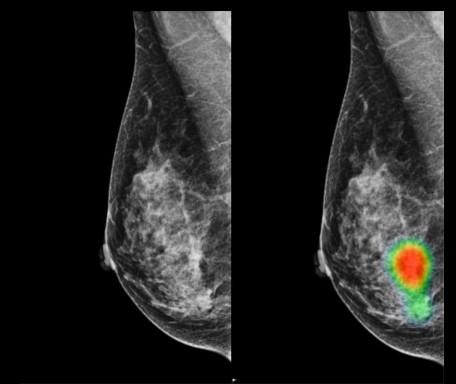

Detecting Breast Cancer

Every year, 11 500 women and 80 men die from breast cancer intheUKalone.Tohelpimprove the situation, Google Health and Imperial College are working on making an AI that can diagnose breast cancer from a mammogram. This would help the estimatedshortageof1000radiologists in the UK as well speed up the diagnosis and hopefully reducemisdiagnosis.

The algorithm was trained wasdesignedandtrainedwithx -rayimagesfromnearly 29000 women. The algorithm outperformed 6 individual radiologists andwasonparwiththecurrent systemoftworadiologistsworking together. However, even moreimpressivelytheAIdidnot have access to patients past medicalrecords.

Mammograms of a 49-yearold woman with carcinoma used in a more recent AI study